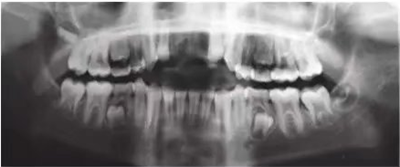

車禍后,一名10歲男孩被送往Shariati醫(yī)院急診科。診斷出上頜中切牙的脫落和側(cè)切牙的嵌入(圖1)。脫落的中切牙丟失了,沒有進(jìn)行再植。全景片示除第二磨牙外的恒牙列(圖2)。

圖2. 初診全景片